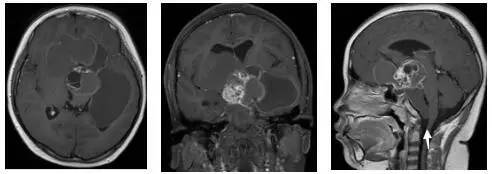

鉴于肿瘤体积超大,而且患儿间断出现意识障碍,直接作手术完全切除肿瘤的难度很大,为降低手术风险,所以我们采用先穿刺肿瘤囊减少肿瘤体积,降低颅压,二期手术争取完全切除肿瘤的策略。行肿瘤囊肿穿刺后,引流出约100多毫升囊液,肿瘤体积显著变小,见图3、图4。

穿刺手术后患儿精神好,调养后3天行开颅手术切除肿瘤,经过14小时的艰苦奋战,顺利将肿瘤完全切除,手术后MRI见图5。患儿共住院23天,顺利康复、出院,出院时语言能力、四肢肌力均正常。

图4.肿瘤囊穿刺手术后肿瘤体积减小

白色箭头示引流管

图5.手术后MRI显示肿瘤无残留迹象